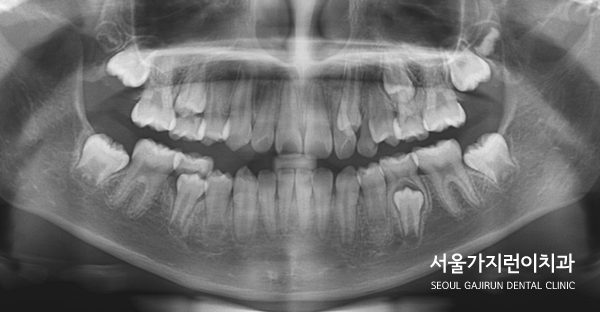

치열이 좁아서 공간이 부족하거나 유치가 제때 빠지지 않은 경우에는 '이소맹출'이 발생할 수 있었는데요. 치아의 맹출 방향 이상, 잇몸 혹은 뼈 내부의 병변, 유전적 및 발달적 용인에 의해 발생할 수 있었어요. 어린이 환자의 경우에는 이소맹출 때문에 좌측 유견치의 뿌리가 흡수되지 않았고 동요도 없는 상태였는데요. 골격적으로 봤을 때 하악골의 과성장 패턴도 보이고 있었어요.

그래서 엉뚱한 자리로 자란 상악 좌측 견치를 제 자리로 이동시키기 위해 잔존한 유견치를 발치했고 해당 자리로 이소 맹출된 견치를 이동시키는 플랜을 수립했었습니다. 어금니를 전방으로 이동시키면 견치를 배열할 공간이 줄어들 수 있었는데 환자의 보호자 분께서 미니스크류 사용을 반대하셨기 때문에 다른 방법을 찾아야 했었습니다. 그래서 환자 분의 경우 TPA(횡구개 아치)를 본딩해 어금니가 이동하지 않도록 잡아주었습니다.

송곳니 치아교정을 진행하면서 어금니가 이동하지 않도록 신경 쓴 부분이었는데요. 유치가 빠지고 영구치가 자라는 과정에 있는 성장기 어린이환자였기 때문에 이 부분도 조심스럽게 접근해 진행하였습니다.

아직 성장 중이라는 부분을 활용해 치아교정을 이용한 케이스에 혹시 모를 상황을 대비했는데요. 상악골이 조금 더 나와보이는 이유는 아이가 하악골 과성장 패턴을 보였기 때문에 잔여 성장으로 자랄 것을 예상하여 맞춘 케이스입니다. 만약 이때 딱 맞춰 교정할게 된다면 앞니의 맞물림이 절단교합 혹은 교차교합으로 될 가능성이 높았기 때문에 이를 방지하기 위해 과수정되게 끝낸 것이죠.